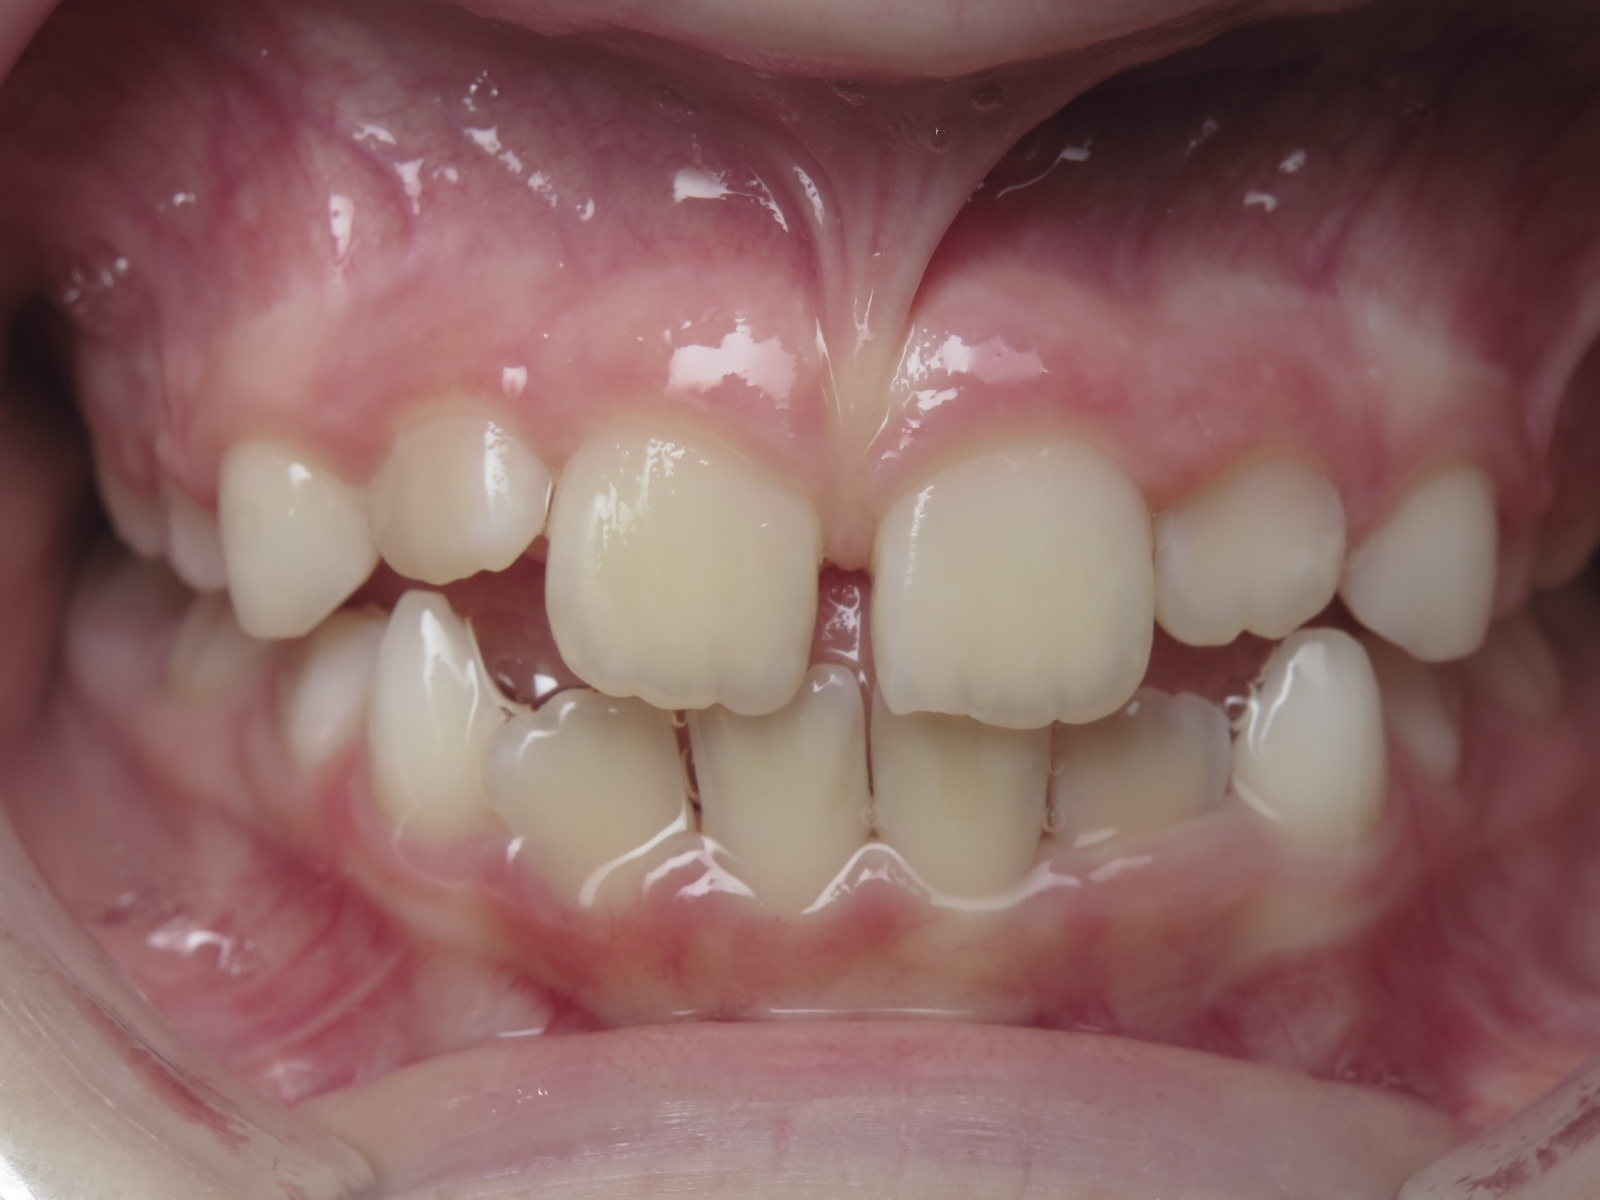

18 béance inversé droit 4 ans

inversion des dents postérieur et espace entre l'arcade du haut et du bas (béance)

bilan de début et en cours de traitement